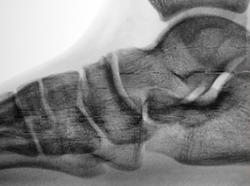

Пол пациента: Мужской пол Тип патологии: Другое Область исследования: Скелетно-мышечная система Методы исследования: Rg Из военкомата. Какие мнения будут по поводу таранно-ладьевидных сочленений? https://radiomed.ru/sites/default/files/styles/case_slider_image/public/user/12/2.dscn1025a.jpg?itok=895Pqsc6 https://radiomed.ru/sites/default/files/styles/case_slider_image/public/user/12/3.dscn1026.jpg?itok=OvSan5Zo https://radiomed.ru/sites/default/files/styles/case_slider_image/public/user/12/4.dscn1026a.jpg?itok=fas3PaIW ID:25966 Ср, 30/01/2013 - 19:11 #1 maker4ik Не на сайте Был на сайте: 8 лет 7 месяцев назад Зарегистрирован: 19.10.2011 - 17:49 Публикации: 2682 Я не очень понимаю при подобной контрастности, но на 2й ноге остеофит больше 1 мм, поэтому можно 2 ст поставить. Ср, 30/01/2013 - 21:31 #2 И.Бондаренко Не на сайте Был на сайте: 1 день 1 час назад Зарегистрирован: 13.09.2011 - 22:55 Публикации: 9206 Очень похоже на добавочные косточки. Если у Королюка есть такие, значит они. Или обызвествление связок. Ср, 30/01/2013 - 23:56 #3 Чижевский Вадим... Не на сайте Был на сайте: 3 года 1 месяц назад Зарегистрирован: 12.11.2008 - 21:21 Публикации: 43 Жалко не показана вся стопа. Похоже, что поперечное плокостопие 3 ст. Артроз 2 ст. Хотелось бы и прямую проекцию посмотреть.

Я не очень понимаю при подобной контрастности, но на 2й ноге остеофит больше 1 мм, поэтому можно 2 ст поставить.

Очень похоже на добавочные косточки. Если у Королюка есть такие, значит они. Или обызвествление связок.

Жалко не показана вся стопа. Похоже, что поперечное плокостопие 3 ст. Артроз 2 ст.

Хотелось бы и прямую проекцию посмотреть.